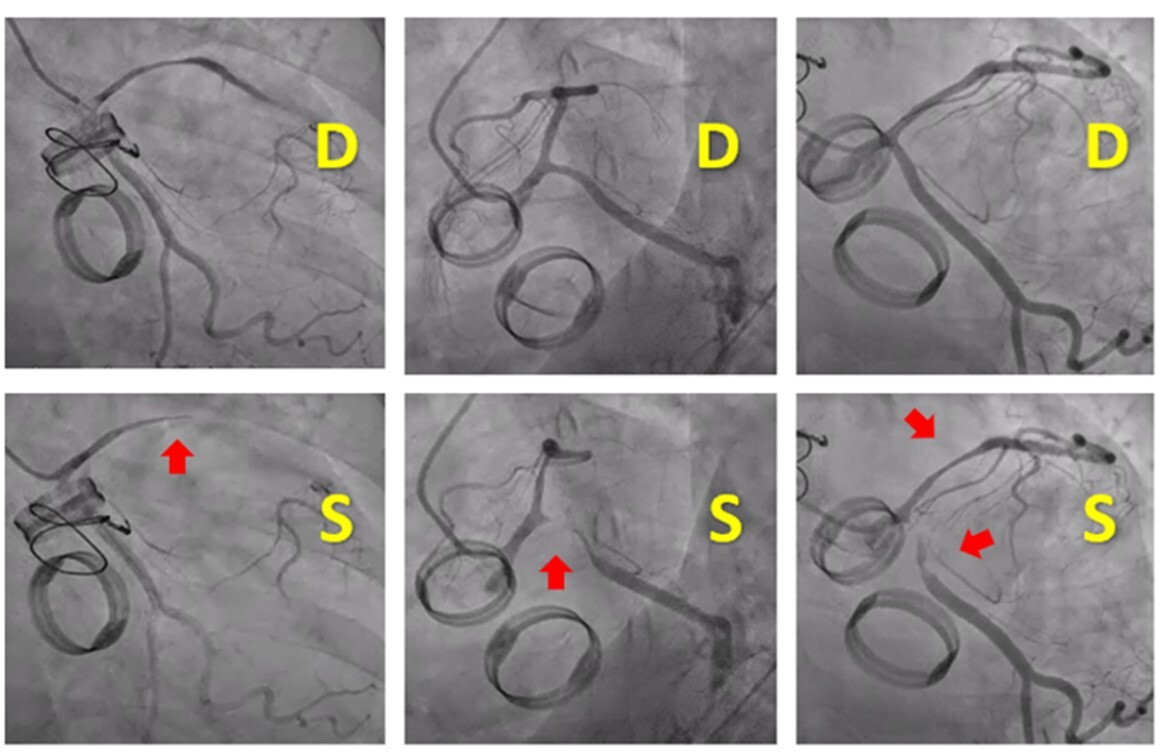

Transesophageal echocardiogram showed a large pulsatile cavity around the aortic root connected to the left ventricle at the level of the anterolateral region of the aortic prosthetic ring, consistent with a pseudoaneurysm. This finding was confirmed by a thoracic computed tomography scan, which showed a large pseudoaneurysm with polylobulated morphology and multiple sacculations that appeared to originate from the upper edge of the mitroaortic junction (Figure 4).